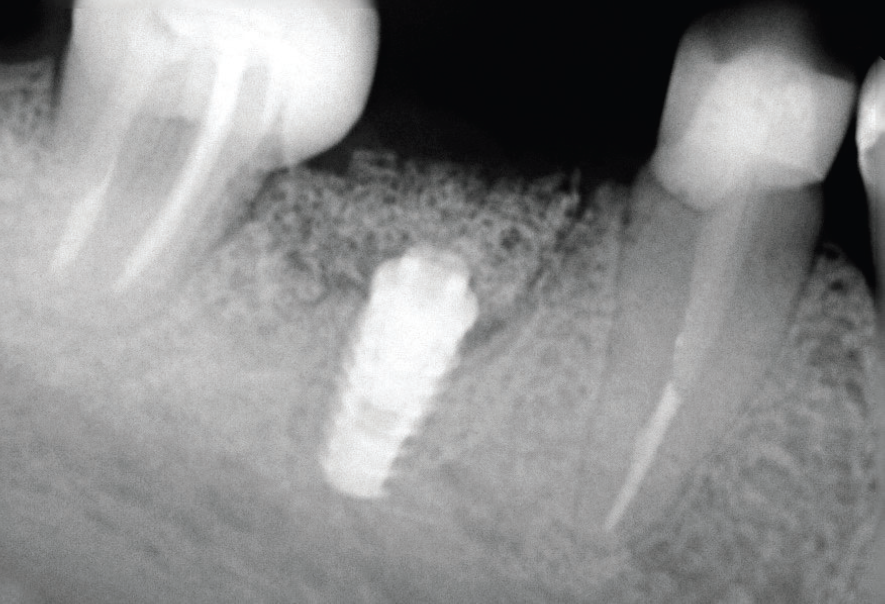

No exame clínico, a sondagem periodontal mostrou 7 mm de profundidade na distal do dente 46, com sangramento à sondagem. Para complementar o diagnóstico, a radiografia periapical do dente 46 apontou uma extensa lesão radiolúcida na raiz distal que apresentava conduto obturado, e a tomografia computadorizada de feixe cônico (TCFC) permitiu a visualização de uma tênue linha hipodensa oblíqua no terço médio da raiz distal, com aspecto sugestivo de trinca/fratura radicular (Figuras 1 e 2).

Para a regeneração óssea guiada, o substituto ósseo natural composto por hidroxiapatita bovina e colágeno do tipo I (Extra Graft XG-13) foi introduzido ao redor do implante para preenchimento do GAP (Figura 7). Depois, uma barreira regenerativa não absorvível (Cytoplast) foi recortada, adaptada e colocada, seguida por uma membrana biológica bovina (Figuras 8 e 9). O procedimento cirúrgico foi finalizado com a realização da sutura com fio de nylon 5.0. Para verificar o posicionamento do implante dentário, uma radiografia periapical foi realizada imediatamente à cirurgia (Figura 10).